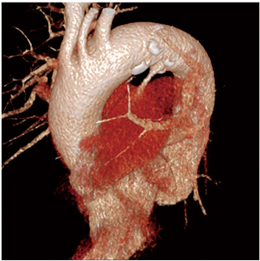

volume rendering(VR)の4Dでは,造影剤が左心室から大動脈に流れていく状態と,PDAの位置を任意の角度から確認することができる(図3)。また,multiplanar reconstruction(MPR)の4Dでは,VRでは確認できない任意の断面の状態や,肺動脈へのジェットの状態を確認することができる(図4)。また,MPRでは,PDAの径を計測することも可能である(図5)。

![]() 図3 PDA症例のVR像 |